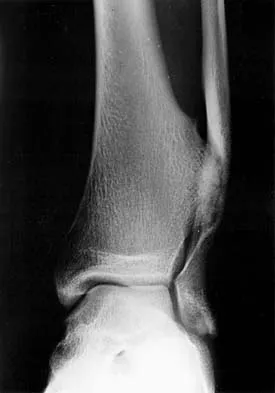

A 78-year-old man being seen for routine follow-up studies reports mild to moderate pain in his left arm. The patient has a history of lung cancer and severe heart disease. A radiograph and a bone scan are shown in Figures 36a and 36b. Treatment should consist of

Explanation